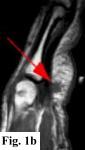

MRI FINDINGS:   MRI was performed on AIC's high-field 1.5 Tesla short-bore Siemens Symphony scanner using a small flexible surface coil. Fig. 1a is a high-resolution coronal DESS, Fig. 1b a sagittal T1 weighted, Fig. 1c a sagittal turbo STIR, and Fig. 1d an axial T1 weighted. They demonstrate a 5x5x7 mm nodule in the volar aspect of the hand at the level of the 4th MCP joint inseparable from the flexor digitorum superficialis tendon (arrows) with some adjacent soft tissue edema. The underlying tendon and bones are otherwise intact.